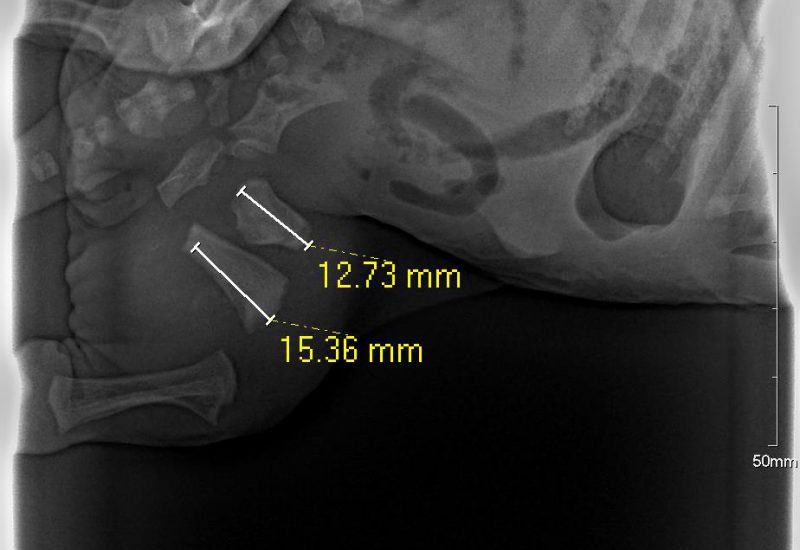

What a brave little girl! This 5 day old Rhodesian Ridgeback puppy was accidentally stood on by her mum and sustained a broken leg (femur). After some very intricate surgery at Hamilton Vetcare, she now has a tiny pin in her leg, and is happily back drinking from mum with her six brothers & sisters.